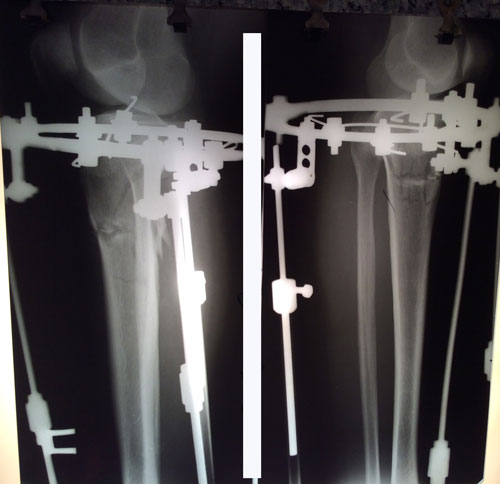

Рентген на фиксации.

IMG_2156-13-02-17-08-48.jpg

IMG_2155-13-02-17-08-48.jpg